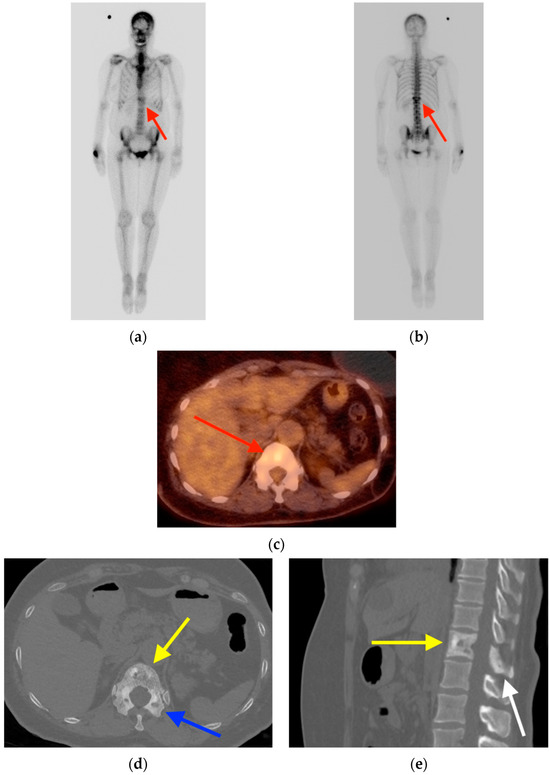

2.4. Schmorl’s Node